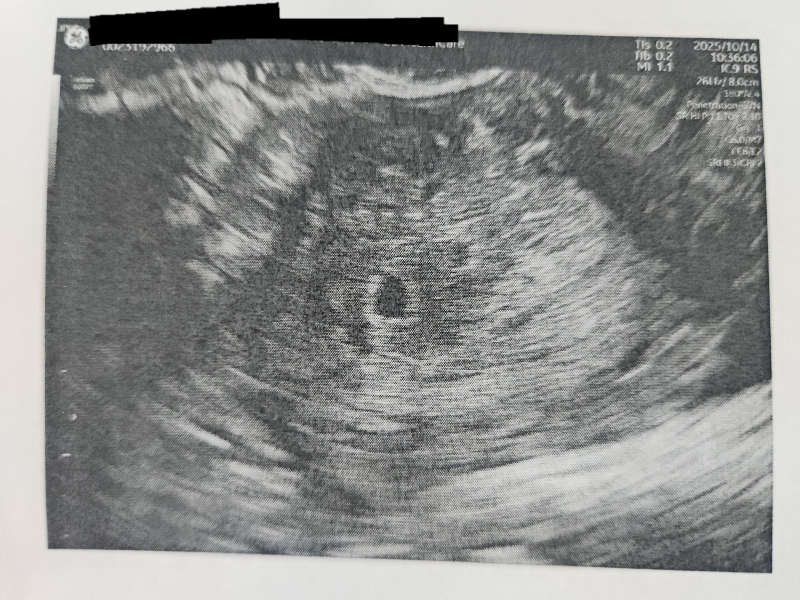

胎嚢が5日前の初診からあまり変わってない。

今日の大きさが6.1mmだそうです。

現段階では、胎芽も卵黄囊も見えず